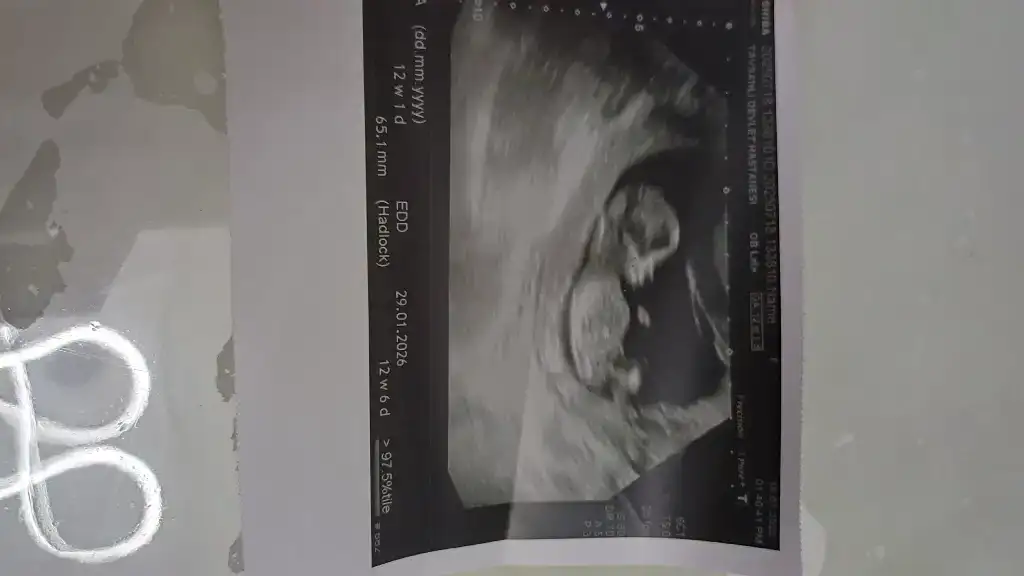

13. Haftaya yeni girdik tahmininiz nedir acaba?

13 haftalik bakarmisiniz nedir sizce